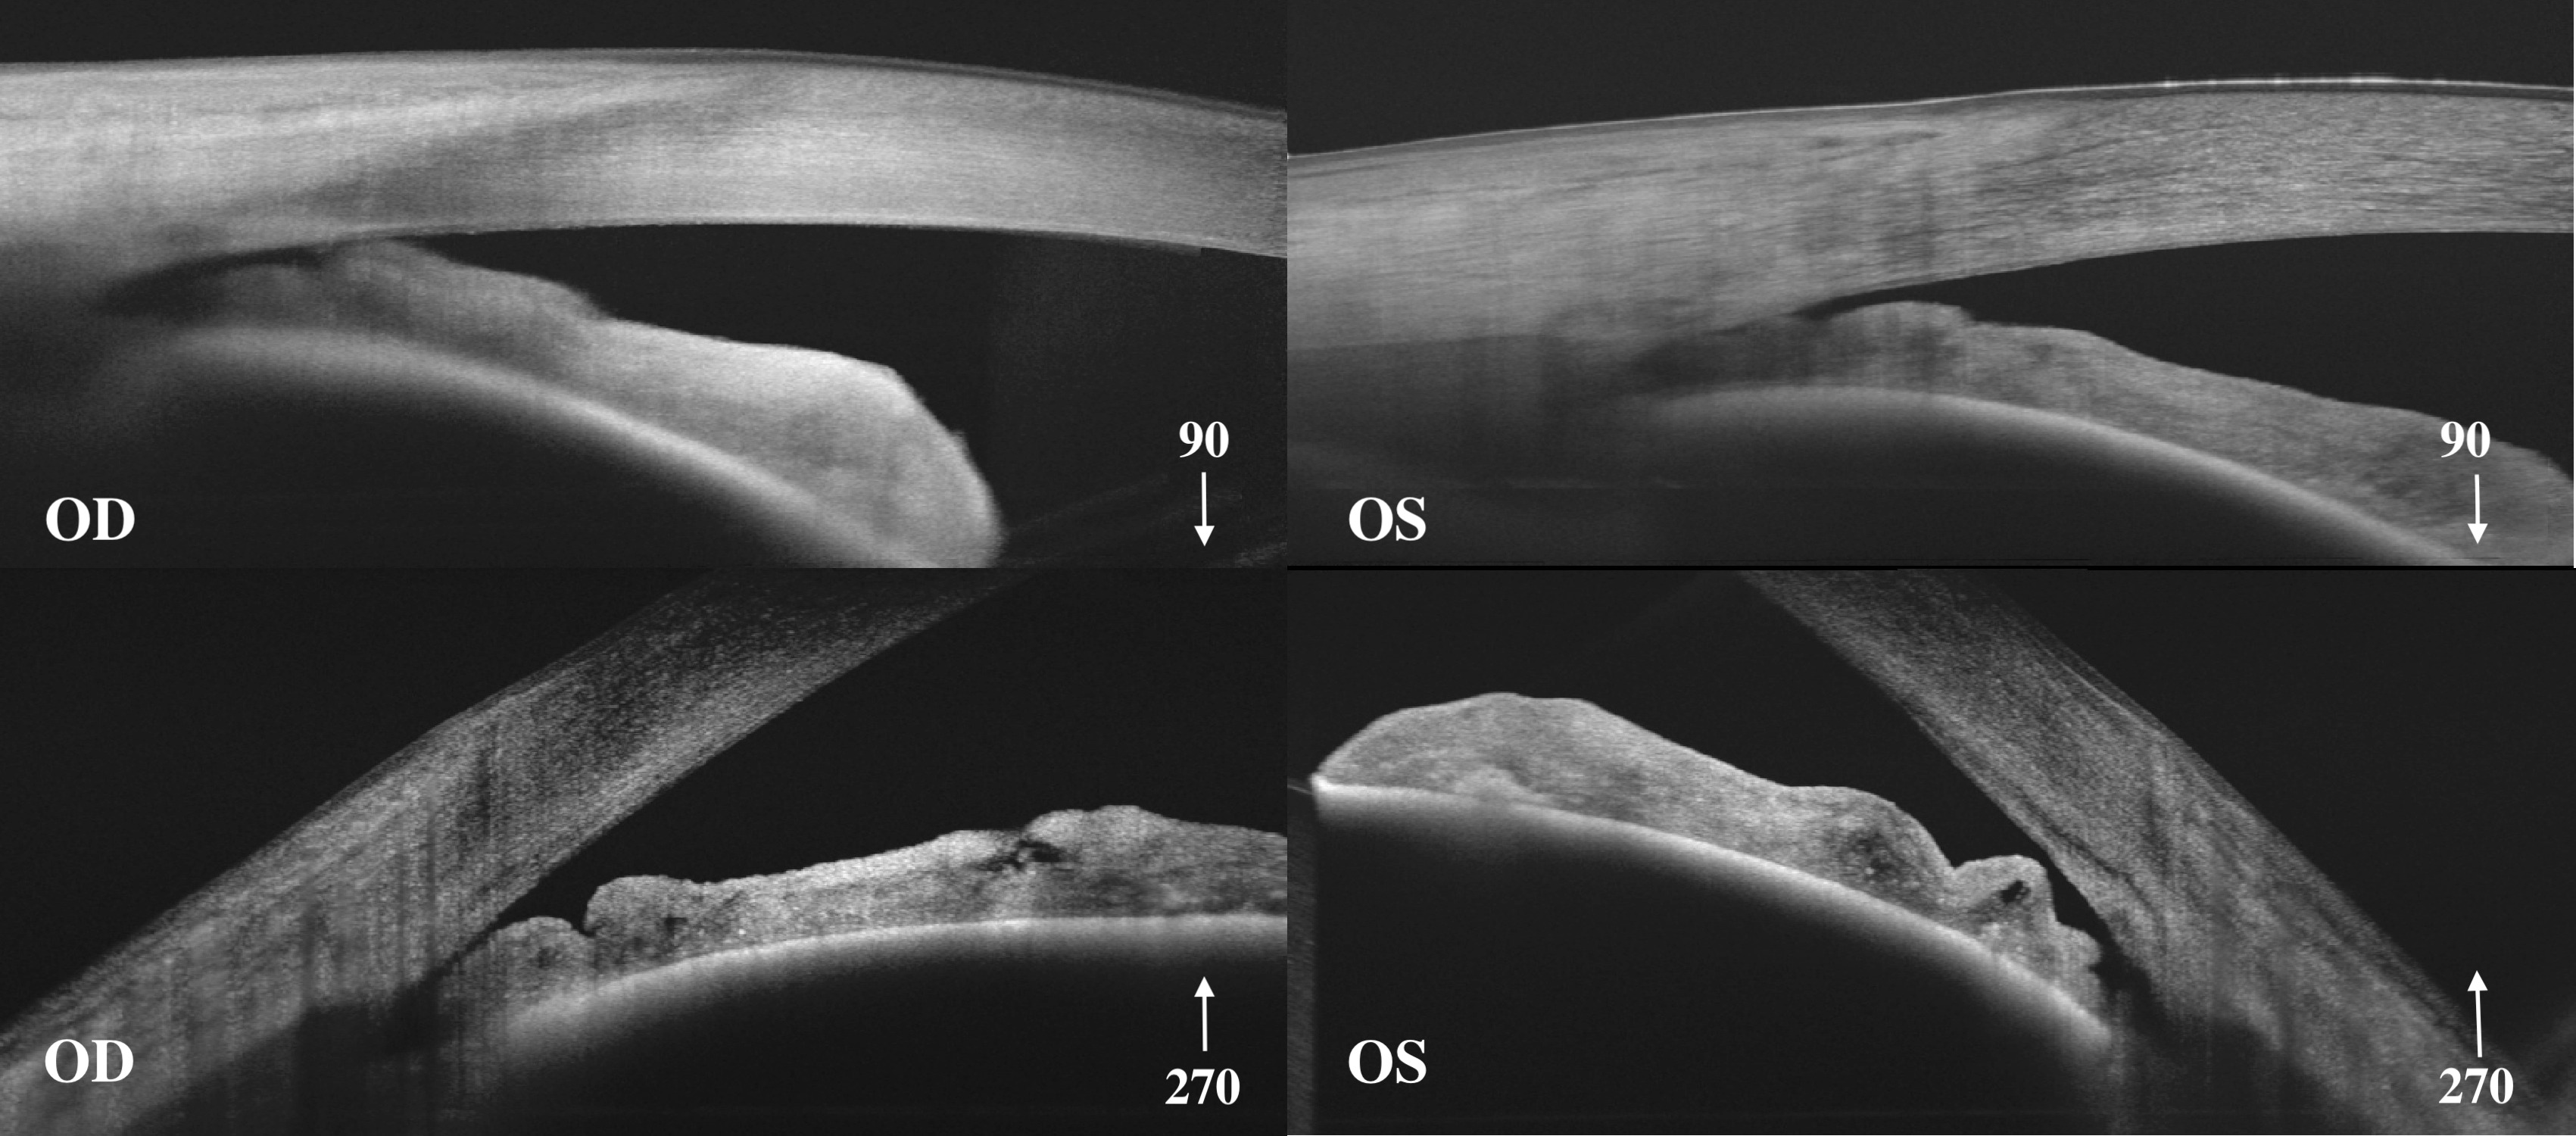

МАТЕРИАЛ И МЕТОДЫ. Представлены три клинических случая на разных стадиях заболевания первичного закрытия угла (ЗПЗУ). Первый связан развитием двухстороннего приступа первичного закрытия угла (ПЗУ) в отделении интенсивной терапии на фоне лечения острого респираторного дистресс-синдрома (ОРСД), связанного с пневмонией COVID-19, у пациентки с ранее не диагностированным ЗПЗУ. Второй случай демонстрирует прогрессирование глаукомной оптической нейропатии (ГОН) при начальной первичной закрытоугольной глаукоме (ПЗУГ) после периферической лазерной иридотомии (ПЛИТ) и отсроченной селективной лазерной трабекулопластики (СЛТ) на фоне увеличения толщины хрусталика. Третий пример иллюстрирует прогрессирование далекозашедшей ПЗУГ на правом глазу (OD) и развитой ПЗУГ на левом (OS), которое было обусловлено формированием гониосинехий после билатеральной ПЛИТ, что потребовало выполнения диодной транссклеральнной циклофотокоагуляции (ДТЦК) на OD и синустрабекулэктомии (СТЭК) на OS. В дальнейшем выполнена билатеральная факоэмульсификация катаракты с имплантацией интраокулярной линзы (ФЭ+ИОЛ) и СЛТ.

РЕЗУЛЬТАТЫ. В первом клиническом случае в течение 2-х месяцев развилась далекозашедшая ПЗУГ на обоих глазах. После двухсторонней ПЛИТ, СТЭК достигнута компенсация внутриглазного давления (ВГД), зрительные функции остались прежними. Во втором клиническом случае через 5,5 лет после ПЛИТ и СЛТ выявлено увеличение толщины хрусталика (OD на 0,2 мм, OS 0,48 мм). На OD ГОН стабильна (скорость истончения слоя нервных волокон сетчатки 0,94 мкм/год, p=0,32, на OS скорость прогрессирования составила -1,04 мкм/год, p=0,018. Учитывая хрусталиковый механизм прогрессирования ЗПЗУ, рекомендована билатеральная ФЭ+ИОЛ. В третьем клиническом примере ВГД оставалось повышенным после билатеральной ПЛИТ, ДТЦК на OD и СТЭК на OS в результате гониосинехиообразования, а потому ФЭ+ИОЛ также не привела к его снижению. После двухсторонней СЛТ достигнута компенсация ВГД без местной гипотензивной терапии (ВГД по данным Icare на OD 18,0 мм рт.ст., OS 15 мм рт.ст.).